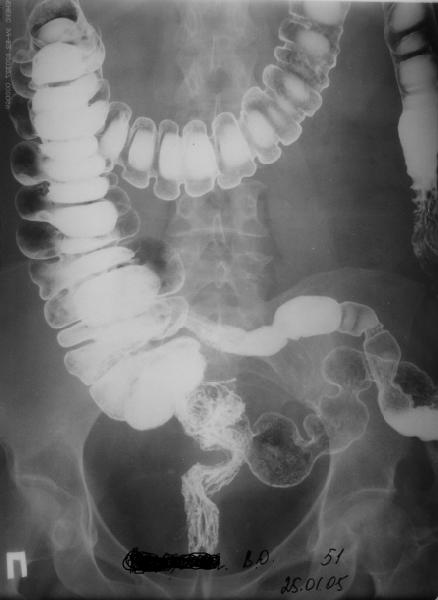

А на мой взгляд - совершенно непохоже. Особенно учитывая ирригоскопию.

1. Если на представленном снимке (ирригоскопия) не перепутаны левая и правая сторона, то судить о выпячивании толстой кишки невозможно, т.к. именно в области предполагаемой грыжи снимок обреан.

2. Даже если толстая кишка и не является компонентом грыжевого мешка, это еще не повод исключать наличие грыжи. В животе много чего может выпячиваться. Поэтому целесообразны последовательные рентгенограмы с пассажем бариевой взвеси через ЖКТ (per os).

Приведенный снимок Ba enema (ирригоскопия?) не показывает / не доказывает наличия патологической дырки в костях таза... Но я согласен с вашим утверждением, что "смысл повторять" отсутствует - во время операции всё станет на свои места..